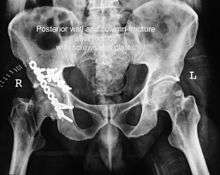

Posterior column with posterior wall / Transverse with posterior wall Fractures

These fractures are extension of elementary fractures. With involvement of posterior wall, the difficulty in treatment increases. These fractures are rarely amenable to non-surgical treatment. Due to posterior wall fracture, the hip is usually dislocated posteriorly, requiring immediate reduction of dislocation and surgical reconstruction after few days.

Cause: Posterior column with posterior wall fracture occurs due to dash board injury, while transverse fracture with posterior wall fracture occurs due to combined dash board injury and direct injury to the hip from the side.

In some cases traction for six to eight weeks may be the only treatment required

If the fragments do not fall into place, or if there are bone pieces in the joint, or if the joint is unstable, surgical fixation using screw(s) and plate(s) is performed

Post-surgery treatment: depending on the stability achieved, the person may be allowed standing and walking with help of support for about six to eight weeks.